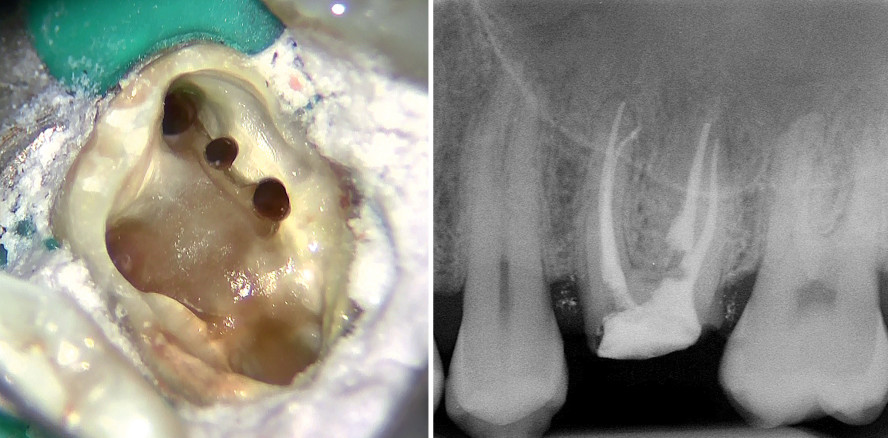

Der 43-jährige männliche Patient erschien in der Praxis zum Entfernen einer einzementierten Prothese auf Zahn 26. Der Zahn war beim Kauen nicht symptomatisch und reagierte negativ auf den Perkussionstest. Auf einer Röntgenaufnahme (Abb. 1), die einige Monate zuvor aufgenommen wurde, war jedoch eine unzureichende Wurzelkanalbehandlung deutlich erkennbar. Die Kanalfüllung war mangelhaft, da die korrekte Arbeitslänge nicht erreicht worden war und die Füllung keine Dreidimensionalität aufwies. Aus diesem Grund wurde entschieden, vor der erneuten prothetischen Versorgung des Zahns zunächst eine endodontische Revision durchzuführen. Die gesamte Behandlung wurde mithilfe eines Operationsmikroskops durchgeführt, um jede Phase der Arbeit mit der größtmöglichen Präzision kontrollieren zu können.

Die neue Zugangskavität zum Kanalsystem wurde mit den Schallspitzen SF66 und SF68 (Komet Dental) bei einer niedrigen Leistungsstufe und unter Zufuhr von reichlich Kühlung neu definiert, wobei störende Faktoren entfernt wurden (Abb. 3). Danach fiel uns eine lang gestreckte Verbindungslinie vom Eingang des mesiovestibulären Kanals in palatinaler Richtung auf. Daher begannen wir jetzt die Suche nach dem zweiten Kanal in der mesiovestibulären Wurzel.2–4 Dank des EndoTracers (H1SML31.205.006, Komet Dental) mit langem Schaft (31 mm) wurde der Boden der Pulpakammer bei größtmöglicher Sicht auf der Suche nach einem möglichen zweiten Kanal in der mesiovestibulären (im Folgenden „MV“) Wurzel abgesucht (Abb. 4). Der EndoTracer wurde mit sanften Bewegungen bei niedriger Drehzahl (200–300/min) eingesetzt und folgte der Verbindungslinie, um Reste des organischen Materials zu entfernen. Dabei wurden drei weitere Eingänge entdeckt (MV2, MV3, MV4). Es lag also ein Molar mit ganz besonderer Anatomie vor (Abb. 5).